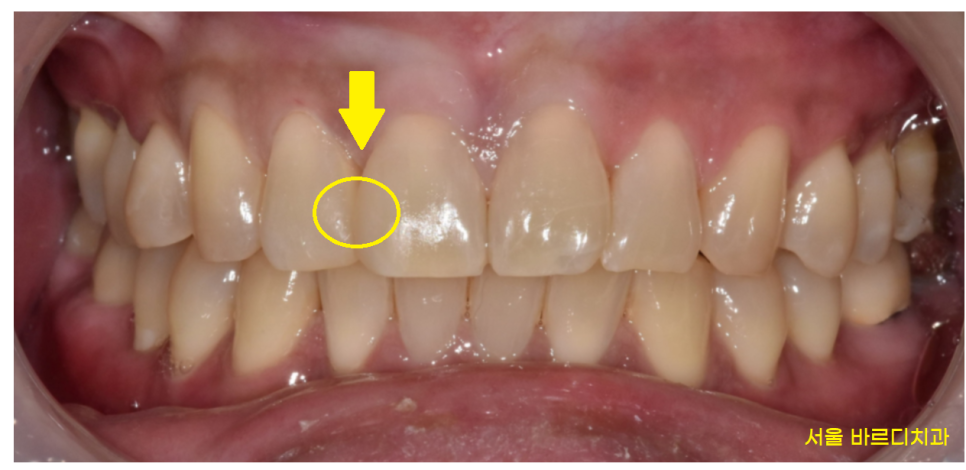

치료결과를 보실까요~?

23.01.30

벌어진 앞니 레진으로 공간을 없애드렸습니다.

사진만 봐서는 어떤게 레진이고

내 치아 부위가 어디인지

구분이 잘 안가시겠죠~??

레진이라는 재료가

치아 색깔과 똑같아서 구분이 잘 안가실꺼에요~

그만큼 심미성이 요구되는 앞니에는

딱! 알맞은 치료입니다.

어디가 변했는지 바로 보이시겠죠~?

앞니 레진은 고도의 집중력이 필요합니다.

심미적이기도 하고

모양을 옆에 치아와 비슷하게 만들어서

티가 나지 않도록 떼워드리는게 중요하거든요~